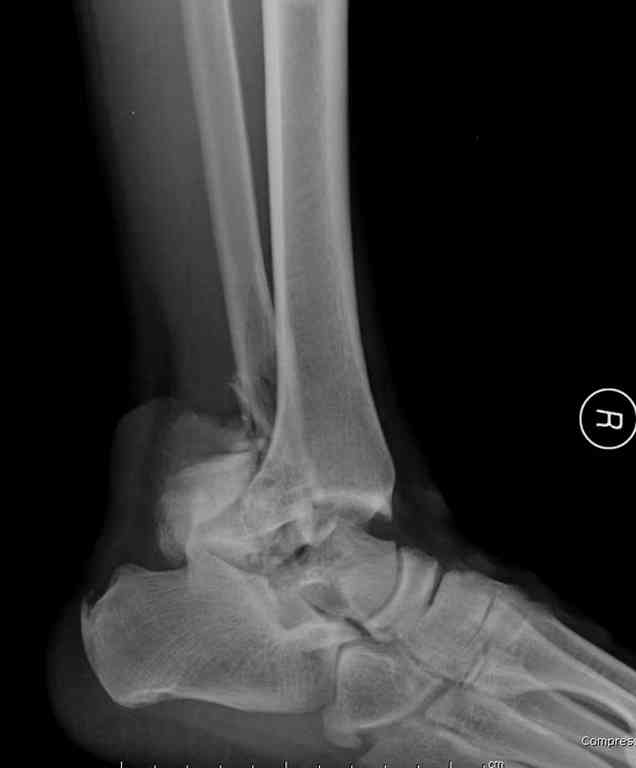

Прошу коллег помочь советом.3 дня назад поступила пациентка 23 года с переломом шейки ладьевидной справа, переломом лодыжек и заднего края б/берцовой кости со смещением и подвывихом кзади, переломом внутреннего мыщелка правого бедра без смещения. Дежурными хирургами проведена репозиция в левом г/ст суставе успешная, попытка репозиции таранной кости ухудшило положение отломков. Планируем провести повторную репозицию и фиксацию винтами. 1. Закрытая репозиция рентгенконтоль интраоперационный (аппарат Арман) ификсация из заднее-наружного доступа. 2. При неудачной закрытой репозиции переходим на открытое вправление двумя доступами медиальным и латеральным "по ходу оси таранной кости" и через дополнительный задний доступ вводим винты кортикальные 4,5 мм или 3,5 мм 3. после открытой репозиции фиксация двумя винтами через боковые доступы погружая их под суставную поверхность Сергей Зырянов ЦРБ Новосибирская область

Переломовывих тарана с повреждением медиальной стороны. Через 4 часа после поступления проведена репозиция и фиксация тарана после Irrigation&Debridment. Частичное несращение медиальной лодыжки не беспокоит, вернулся к активному образу жизни. Полная нагрузка разрешена через 11 недель. Финальные снимки через 11 месяцев.

Второй случай прооперирован вчера.

10 дней назад поступил с открытым повреждением медиальной лодыжки и переломо вывихом таранной кости. Ургентно сделана репозиция с наложением наружного фиксатора + Irrigation&Debridment.